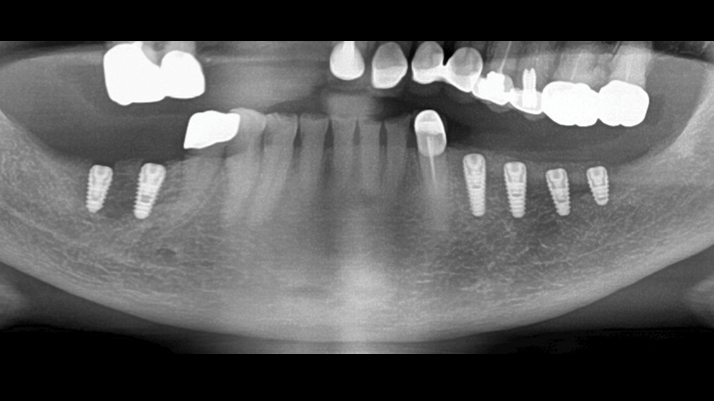

Clinical case: Ridge splitting technique using SmarThor + AnyRidge as expander

- Courtesy of Dr.Kwang-Bum Park, Korea -

Keywords

AnyRidge, ridge splitting, GBR, Dr. Kwang-Bum Park, mandibular posterior, SmartThor, Mega-Oss, thin ridge, bone regeneration

Products:

AnyRidge implant system. SmarThor, Mega-Oss